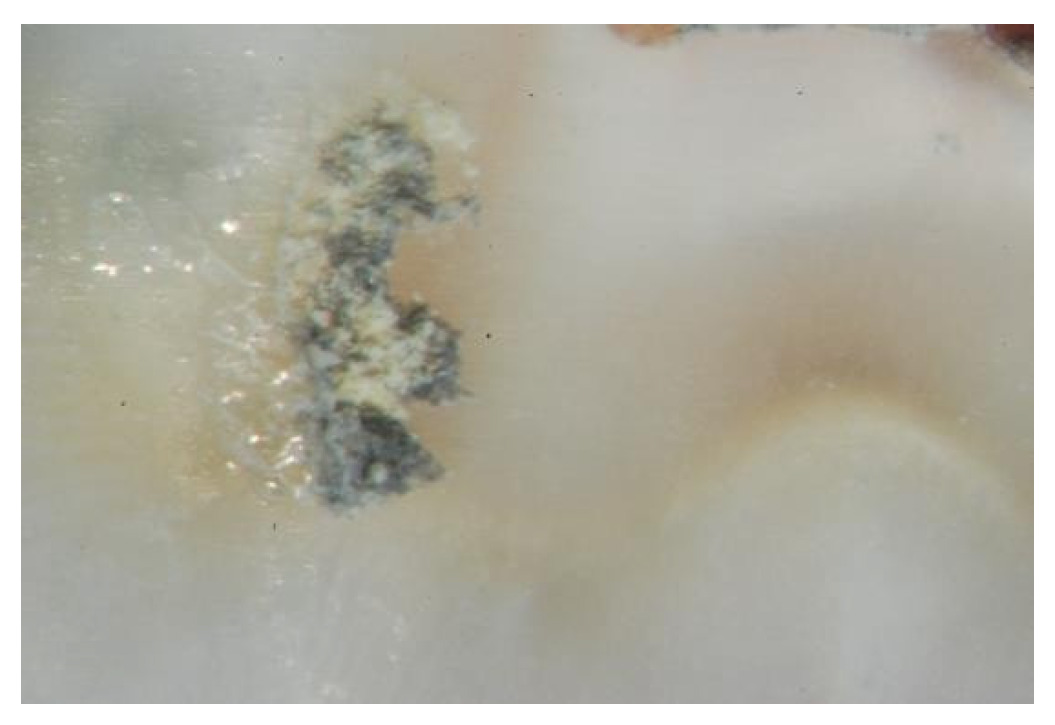

| Material | Adhesive Failure | Cohesive Failure | Mixed Mode Failure | Confidence Interval |

|---|---|---|---|---|

| AH26 | 27 (77.1%) | 5 (14.3%) | 3 (8.6%) | 95% |

| AH26 + DMSO | 25 (71.5%) | 6 (17.1%) | 4 (11.4%) | 95% |